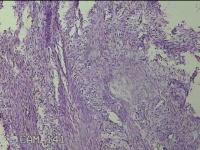

子宫肌瘤结节

多发性子宫肌瘤 继发性不孕症 子宫Ⅰ度脱垂 高脂血症 胆囊息肉

一般病史

发现子宫肌瘤4年余,继发不孕3年。

标本名称

大体所见

灰白暗红色圆形肿物10x9x2.8㎝九个,表面糜烂,切面均为灰白色结节状或编织状,质中。

良性病变。

考虑平滑肌瘤。